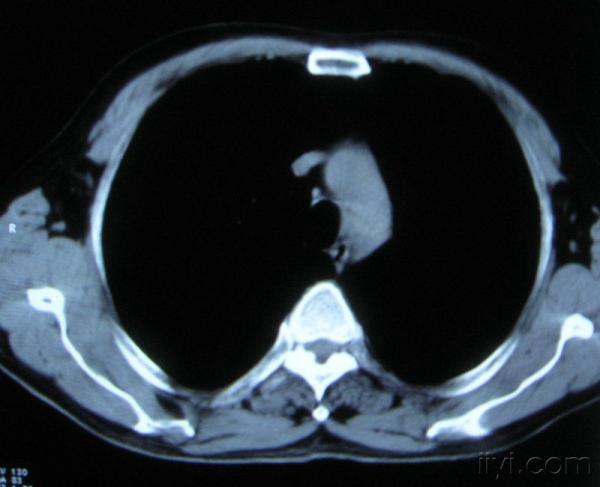

男。60岁,胸片示支气管炎治疗后复查CT。

你指那个肯定是淋巴结,中央系坏死,这很常见,特别在双侧腹股沟会经常看到。这个双侧腋窝及纵隔见多发小淋巴结征。

根据位置考虑应该是淋巴结,密度不均,是因为肿大的淋巴结中心液化坏死